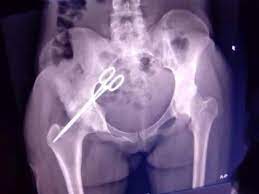

Zainab Kamara only knew she had the instrument in her abdomen at the Kambia Government Hospital after a pelvic X-ray was conducted but could not withstand having the surgery there because according to her, she identified one of the doctors that conducted her original surgery in 2014.